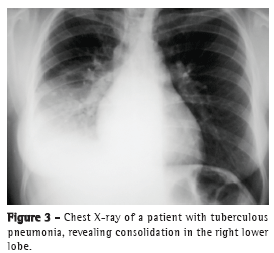

The most common radiological findings are reticular infiltrates and consolidation,(5,6,10,15,17) and cavitation can occur in 27-50% of cases.(6,10,16) Figures 1 to 4 show some of the main radiological patterns in this context.

The time from onset of symptoms to initiation of antituberculosis treatment has been reported to be over 30 days in 28.8-34.0% of cases.(6,17) The time from admission to initiation of appropriate treatment was evaluated in only one study, which reported a mean of 4.3 days. In that retrospective study, the time from admission to initiation of treatment was shorter in patients with miliary tuberculosis than in those with tuberculous pneumonia (2.8 ± 2.5 days vs. 5.0 ± 7.0 days; p = 0.048).(16) There can be a delay in diagnosis and, consequently, in initiation of treatment because it is difficult to differentiate tuberculous pneumonia from severe bacterial pneumonia on X-rays. Considering this difficulty in distinguishing the two pathologies, one study evaluated the differences between ICU patients with severe pneumonia and tuberculosis and those with severe pneumonia without tuberculosis in terms of their clinical and radiological characteristics. Symptom duration longer than two weeks and the presence of micronodules or a cavitary pattern on chest X-ray were significantly associated with active pulmonary tuberculosis.(20) In addition, a miliary pattern on chest X-ray can also be misinterpreted as congestive heart failure.(18)

In view of the aforementioned facts, the role of chest X-ray in the clinical diagnosis of pulmonary tuberculosis in ICU patients remains uncertain, and it is possible that chest X-ray does not contribute as much as expected. In a case-control study evaluating 89 patients with pulmonary tuberculosis and 89 controls, the most common radiological pattern was consolidation, which was found in 61 patients (6.5%). In the multivariate analysis, a history of pulmonary tuberculosis was associated with clinical suspicion of tuberculosis, although the radiological patterns were not associated with that suspicion.(21)